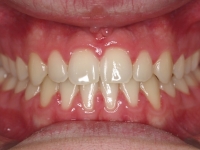

Fotos antes/después

Chica de 17 años tratada en 1 año con stripping en los dientes inferiores